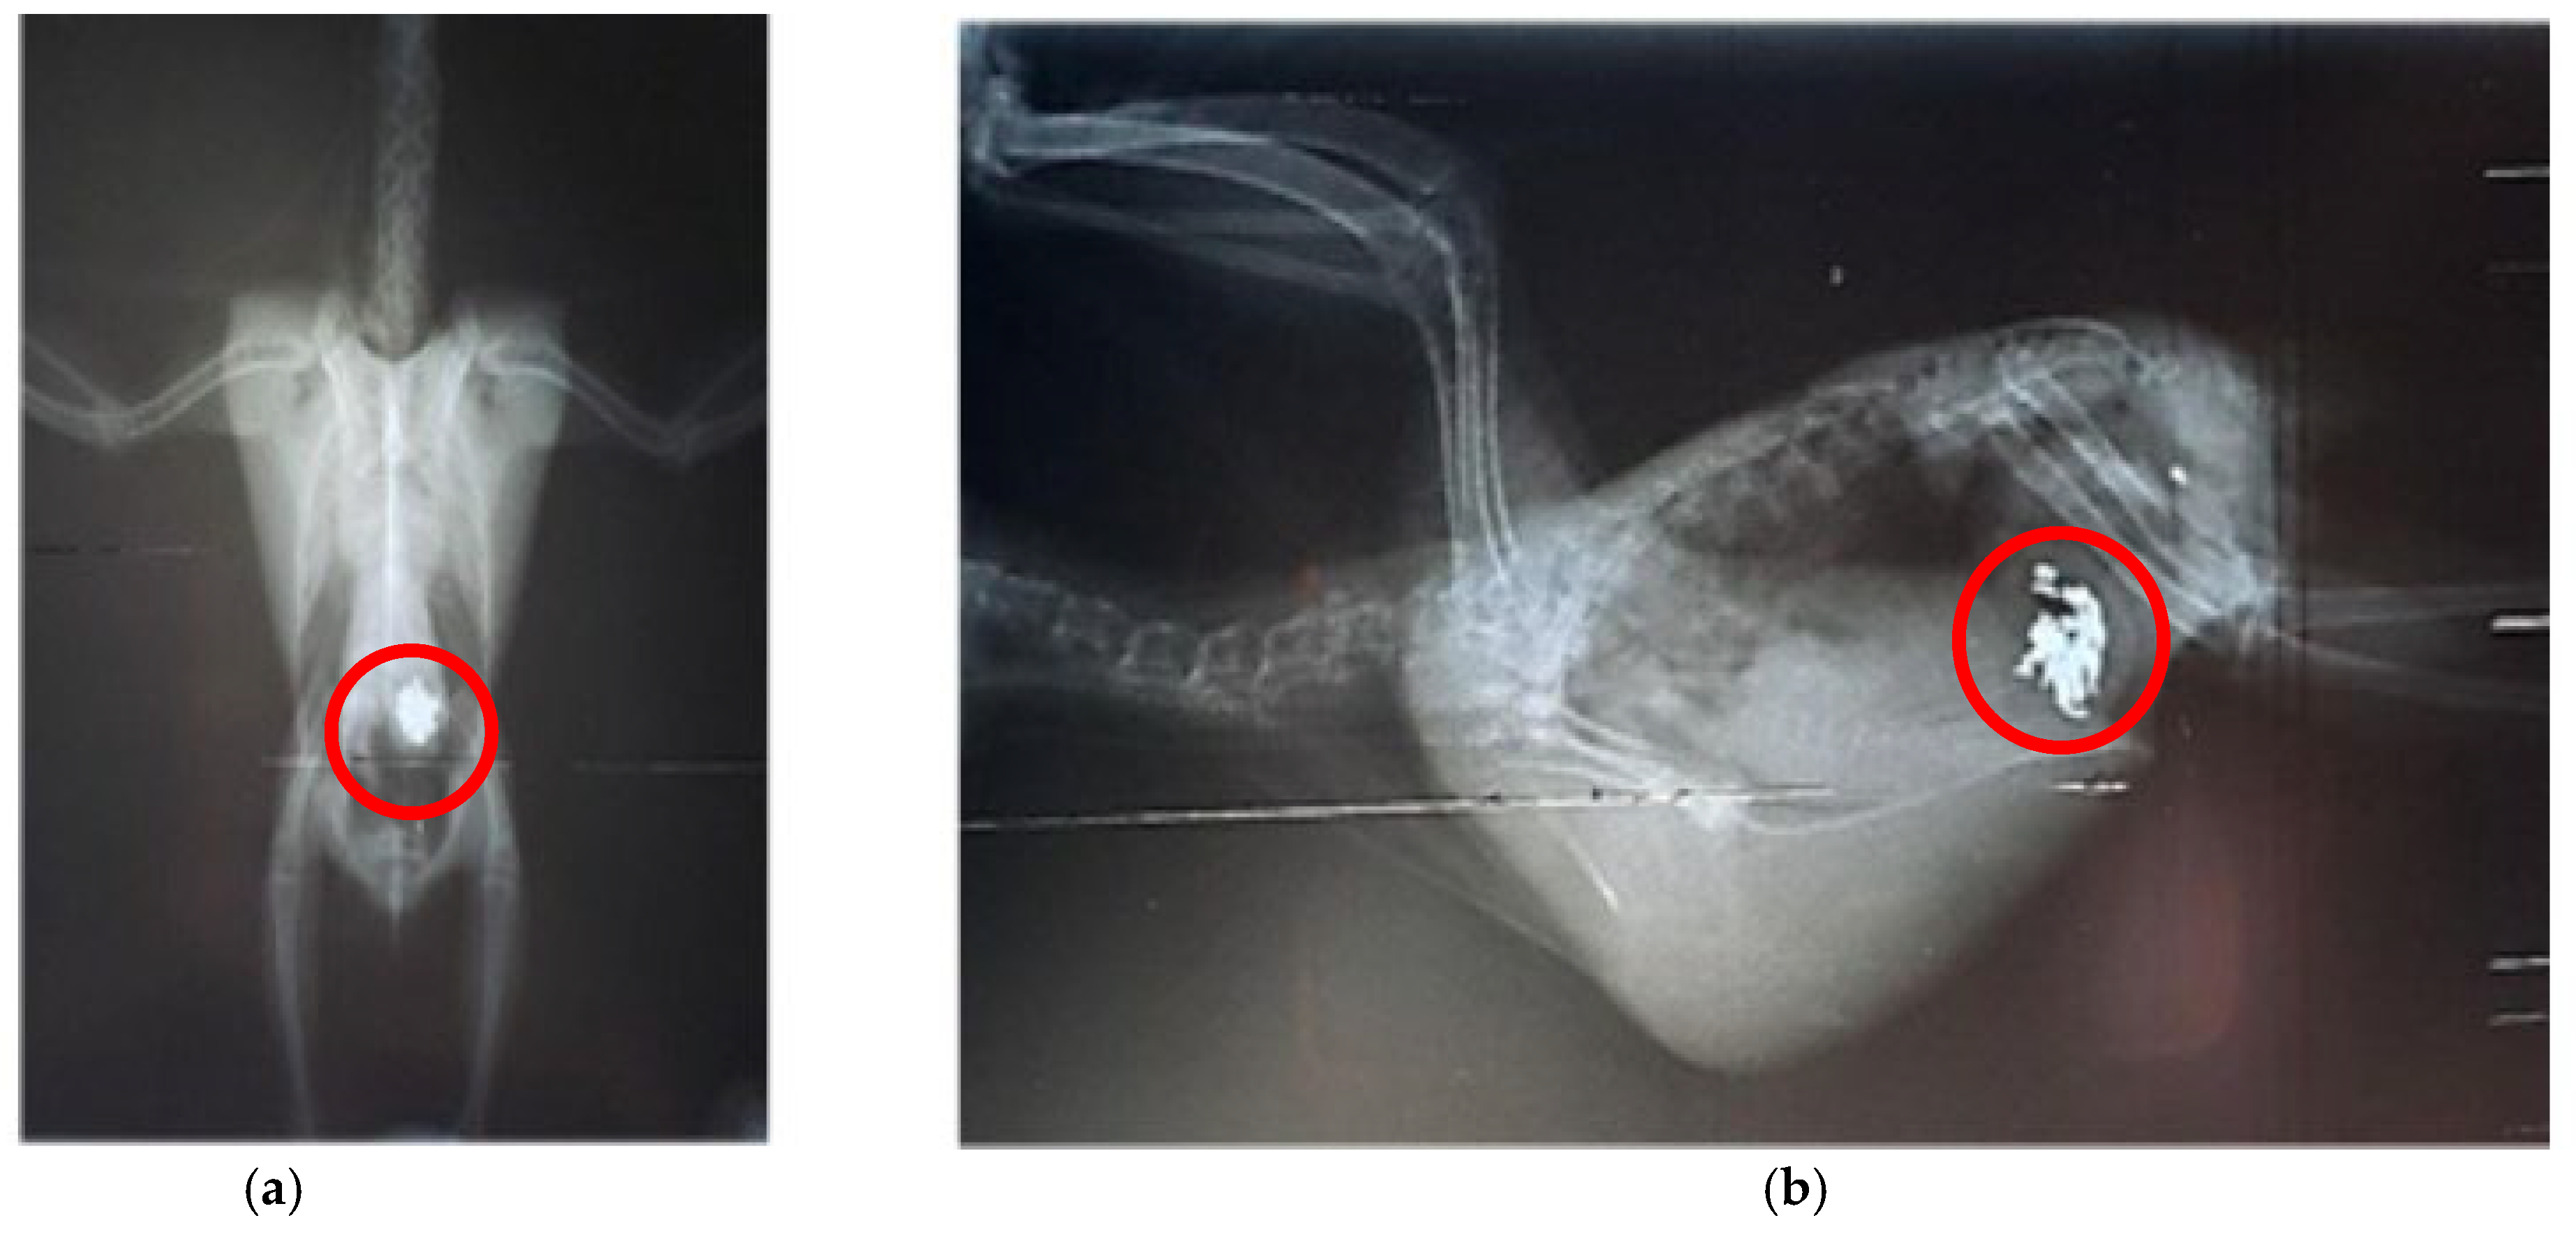

A similar case was described by Pinheiro et al [29] in Nymphicus hollandicus, which also culminated in clinical improvement due to prompt symptomatic treatment, demonstrating that even psittacids known to be domestic and/or in direct contact with humans are more susceptible to heavy metal exposure. Santos et al [31] also detected the presence of radiopaque content (Figure 3) and incoordination in free-living Brotogeris chiriri that responded well to treatment against heavy metal intoxication, restoring full function to the animals. It is important to note the scarcity of reports with descriptive diagnoses regarding the type of metal found, which is a focal point of importance to be better determined in the care of these individuals despite the difficulties in collection and testing, aiming for more accurate treatment directed at the underlying cause. Cases in companion or urban-adapted psittacids, such as Nymphicus hollandicus [29] and Brotogeris chiriri [31], illustrate that even species living in close proximity to humans are not exempt from environmental exposure to heavy metals. On the contrary, these birds may be at elevated risk due to contact with anthropogenic materials in domestic or peri-urban environments. Moreover, because they are under closer human observation, intoxication symptoms are more likely to be recognized and reported compared to free-ranging individuals.

Figure 3. Radiography of the celomic cavity performed in Brotogeris chiriri. (a) Right lateral–lateral position demonstrating the particle with high radiopacity; (b) ventro-dorsal position demonstrating the particle with high radiopacity. Adapted from Santos et al. [31].